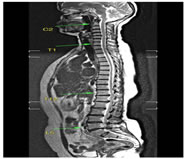

CASE 5

T1W AXIAL IMAGE SHOWING DIFFUSE DISC BULGE, LIGAMENTUM FLAVUM HYPERTROPHY AND BILATERAL FACETAL ARTHROPATHY CAUSING SEVERE THECAL SAC STENOSIS

T2W MID SAGITTAL IMAGE SHOWING MINIMAL RETROLISTHESIS OF L2 OVER L3 AND DISC DEGENERATION AT ALL LUMBER INTERVERTEBRAL LEVELS WITH REDUCED DISC HEIGHT AT FEW LEVELS. THERE IS DISC PROTRUSION NOTED AT L2-3, L3-4, L4-5 LEVELS CAUSING INDENTATION OVER THECAL SAC